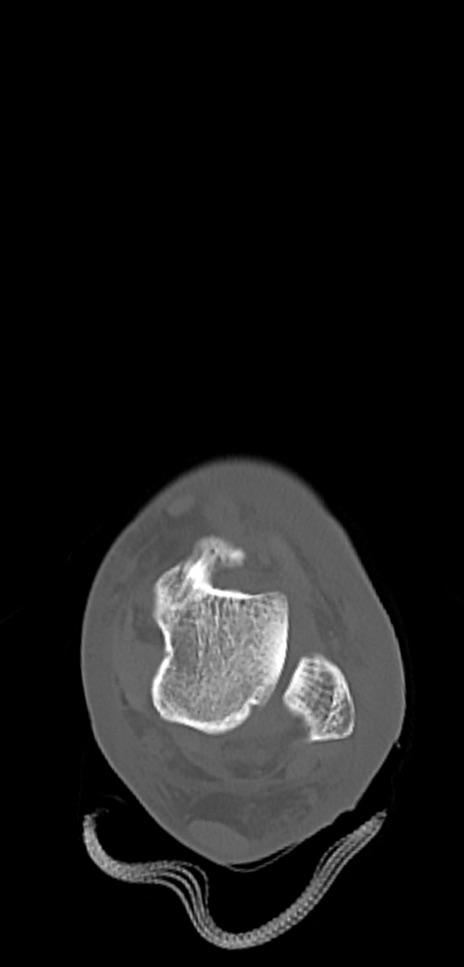

症例37 左足関節CT(横断像)

左足関節CT